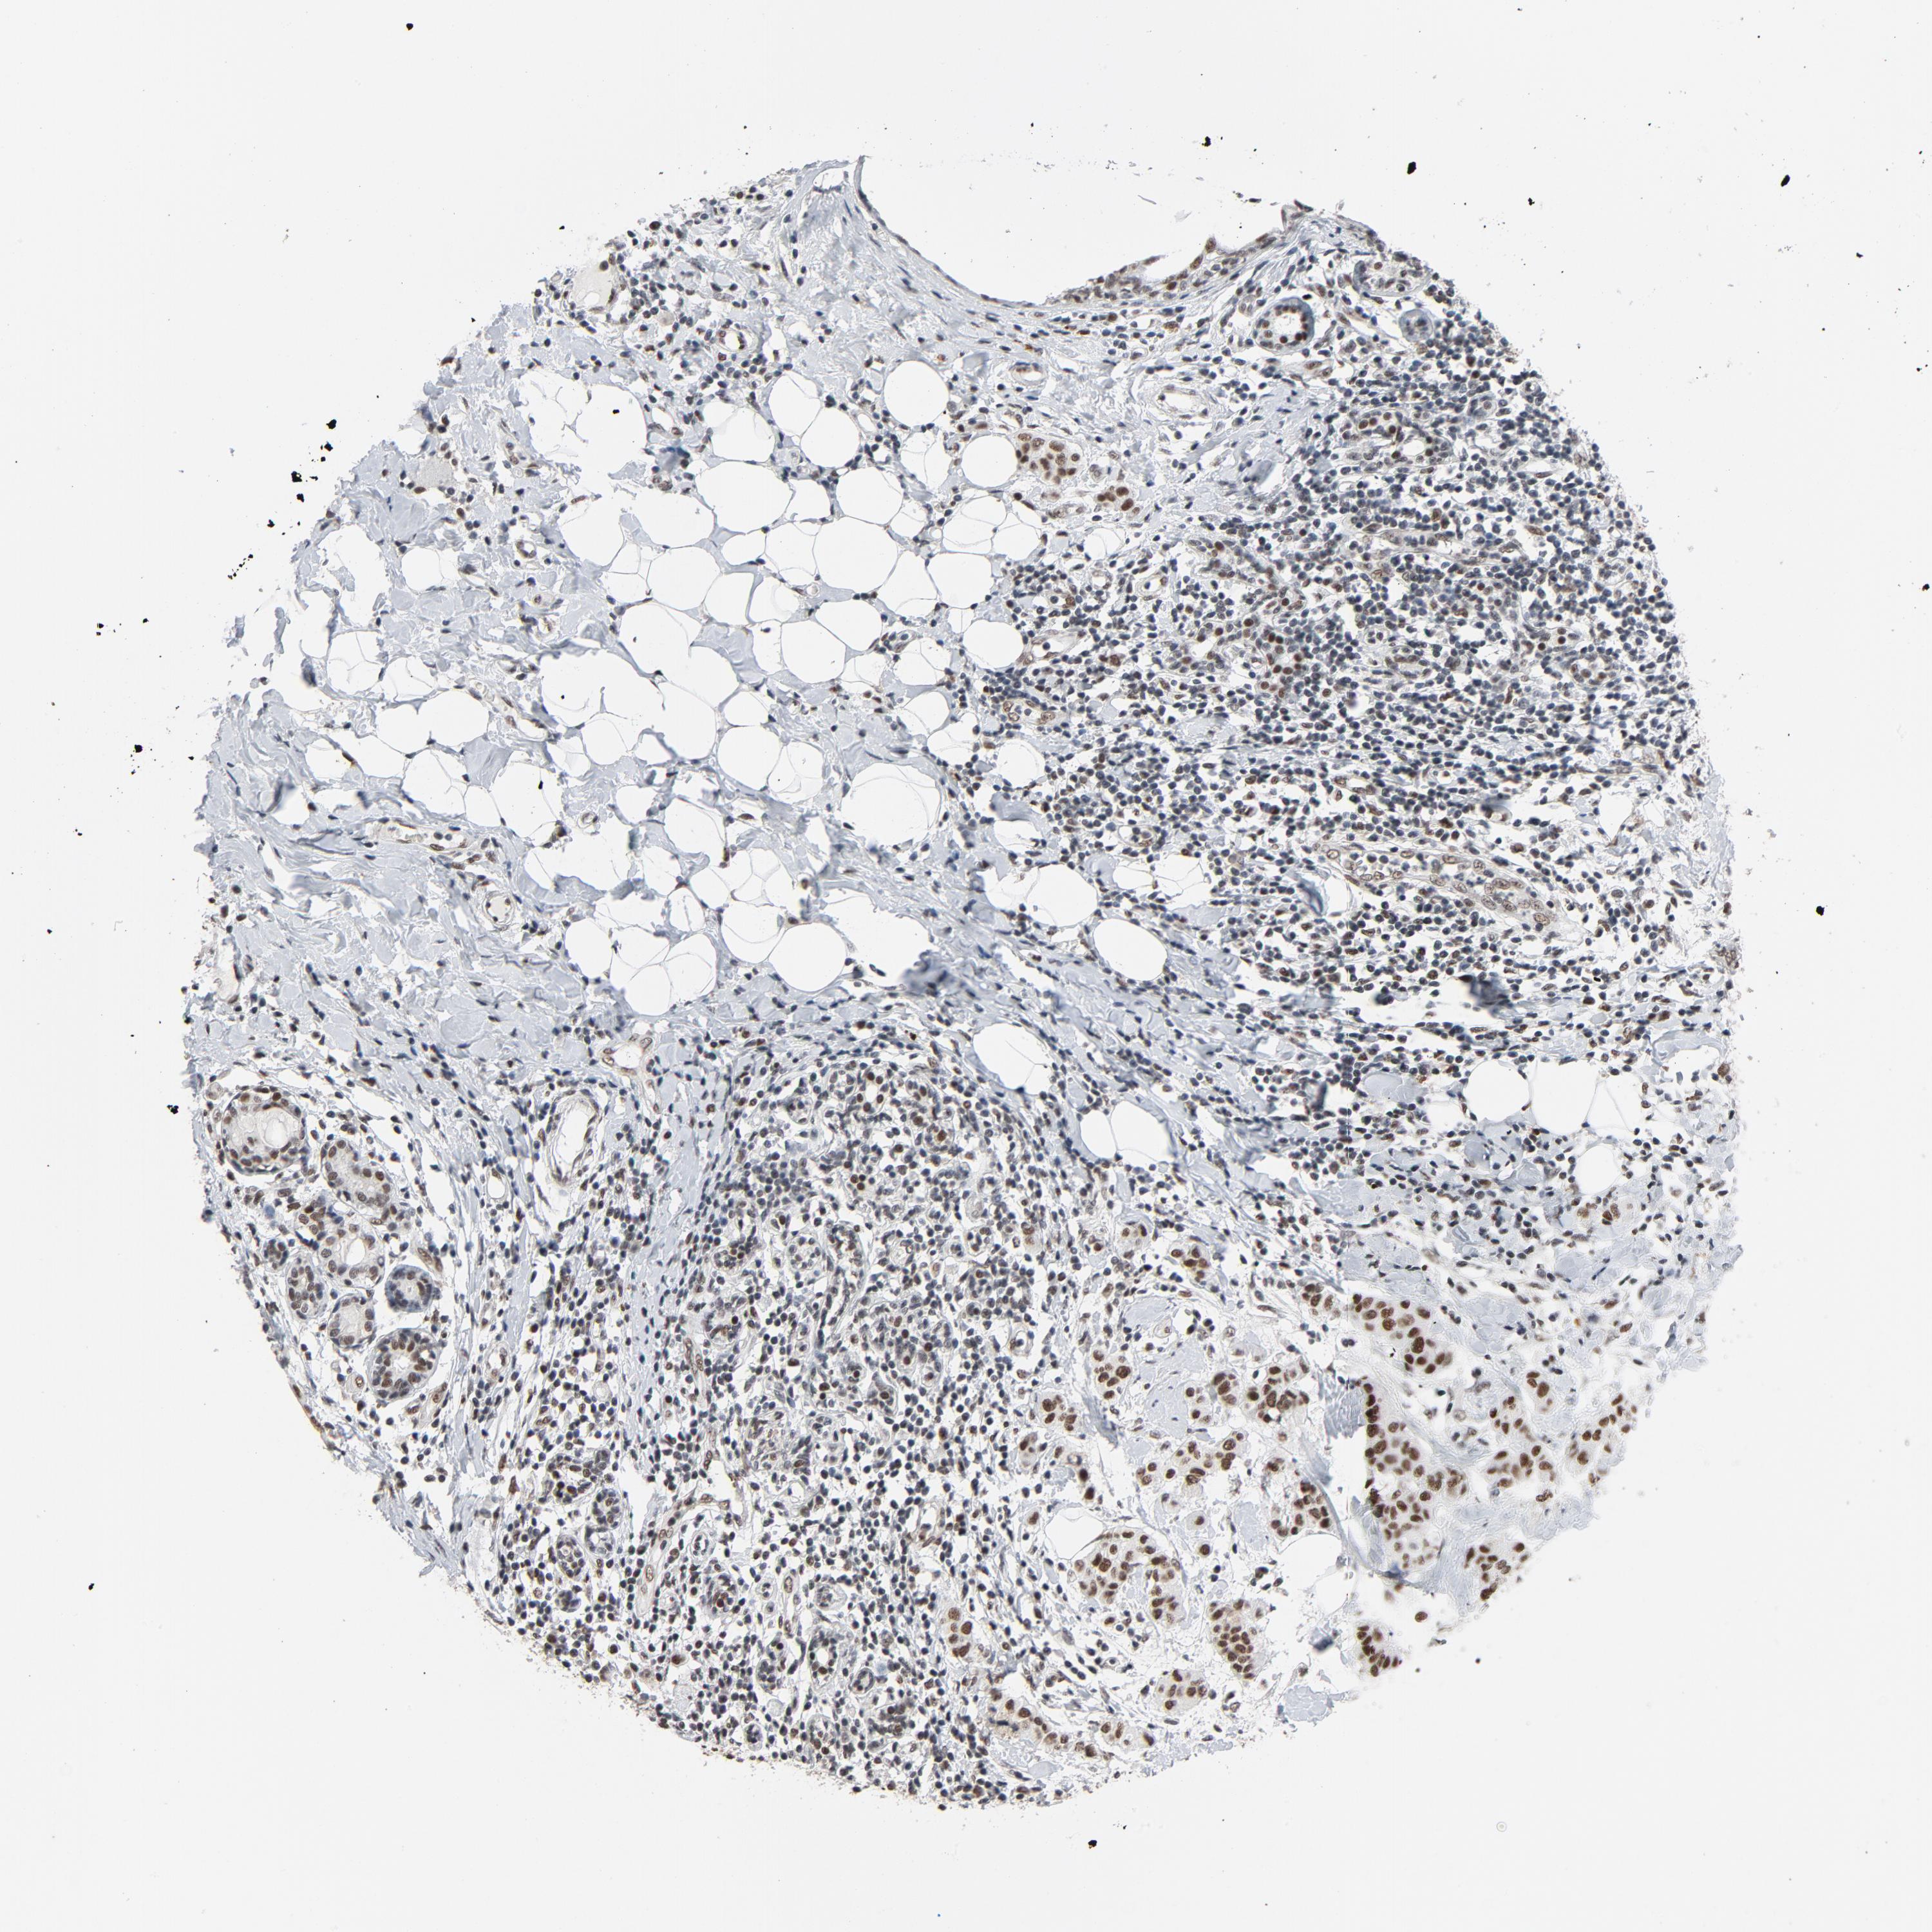

CANCER BREAST CANCER Show tissue menu

BRCA TCGA BRCA VALIDATION PROTEIN EXPRESSION